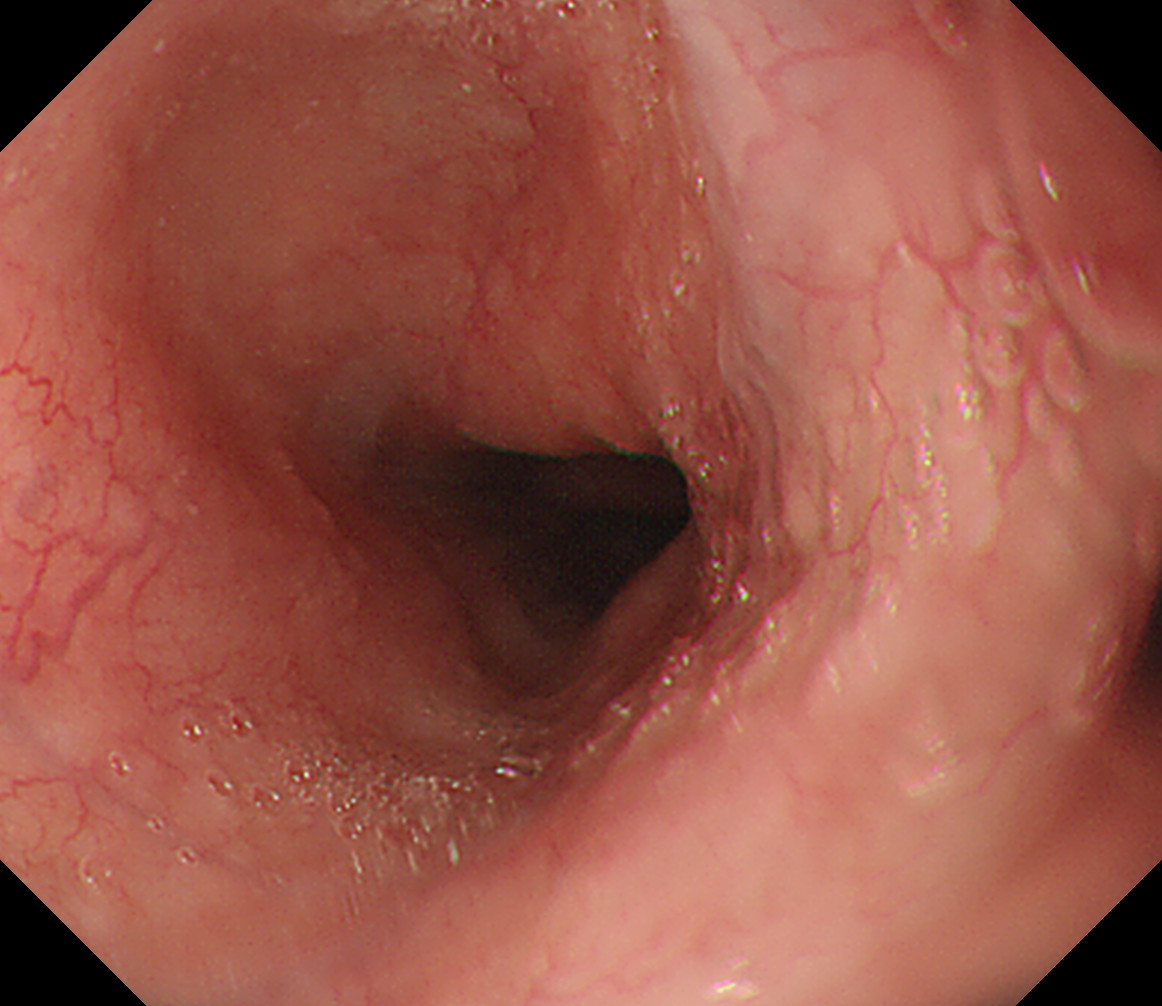

3 EGJ この人はLos-Angeles分類 GradeDの逆流性食道炎があります。 EGJ